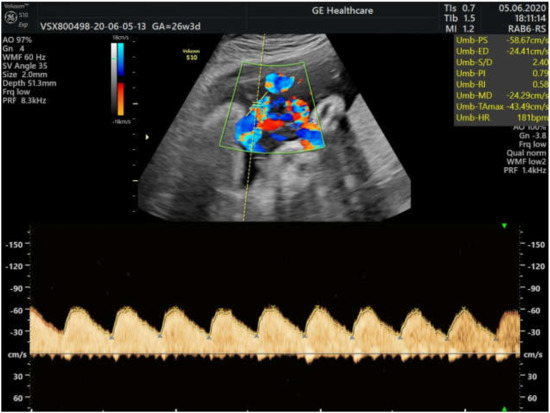

2. Case Presentation